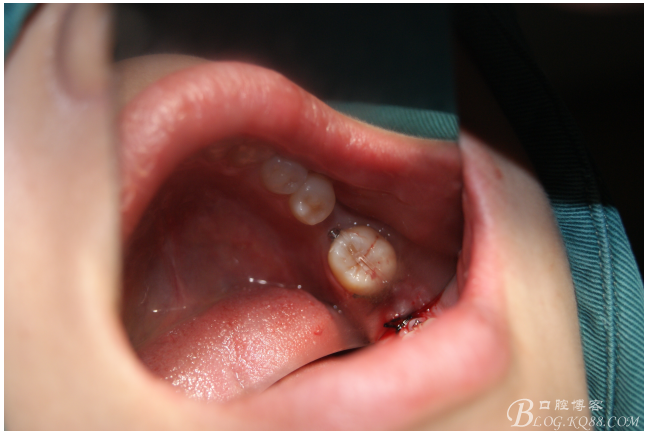

處理:必蘭麻局部麻醉切開(kāi)37遠(yuǎn)中牙齦,植入mini支抗釘一枚,37近中鄰面粘舌側(cè)扣,皮鏈輕力牽引,3周更換。

三月后37扶正

植入5.0X10mm植體